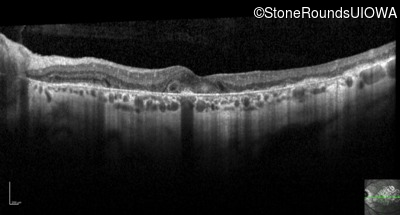

Optical Coherence Tomography - Right - 20/25

Exemplar / OCT Stack

OCT Stack